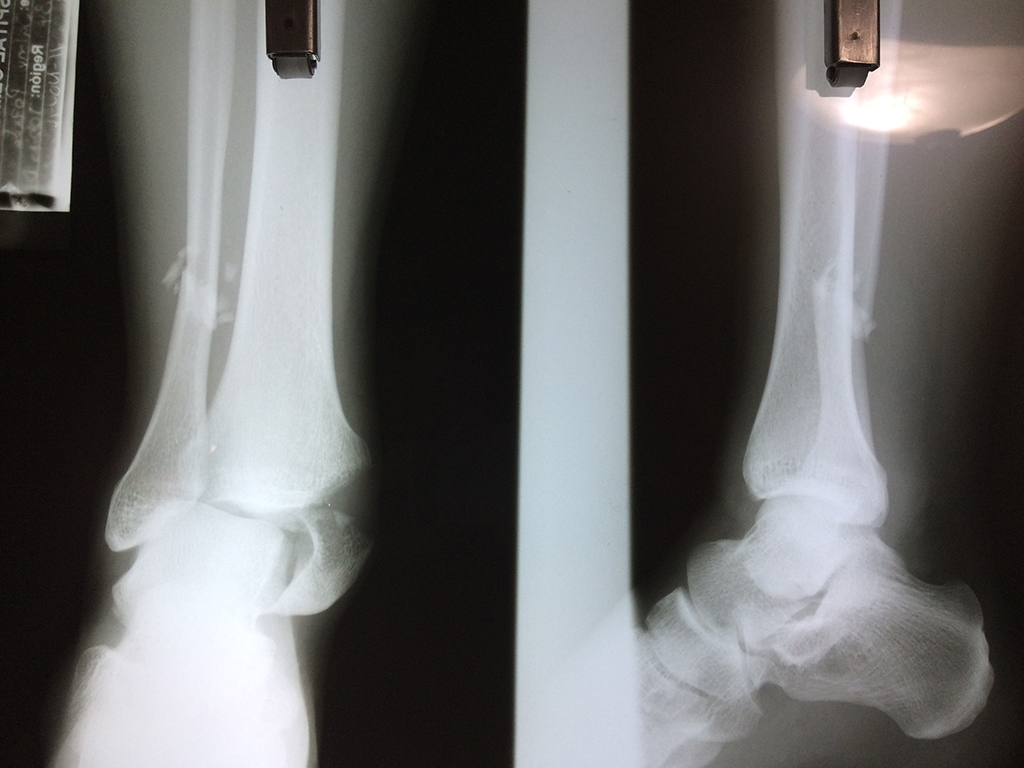

Una fractura de tobillo es la rotura de uno o más de los huesos del tobillo. Estas fracturas pueden ser:

- Producirse en uno o ambos lados del tobillo.

Algunas fracturas de tobillo pueden requerir cirugía si:

- Los extremos de los huesos están desalineados entre sí (desplazados).

- La fractura se extiende hasta la articulación del tobillo (fractura intra-articular).